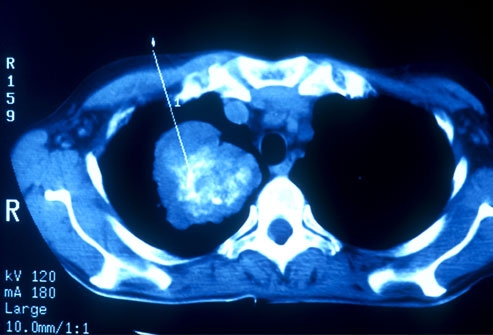

Ung thư phổi có thể được phát hiện sớm bằng chụp CT. Ở Mỹ, có một số đối tượng được khuyên đi sàng lọc ung thư phổi như những người hút thuốc hay có người thân nghiện thuốc, sống trong môi trường ô nhiễm, những người từ 55 đến 80 tuổi được khuyến cáo đi sàng lọc ung thư phổi. Nếu bệnh nhân có tiền sử hút thuốc lá nên định kỳ đi kiểm tra sức khỏe phổi. Ở những người trẻ nếu dừng hút thuốc trong vòng 15 năm có thể ngừng khám sàng lọc ung thư phổi.

Trong hầu hết các trường hợp, khi bác sĩ nghi ngờ bệnh nhân mắc ung thư phổi với các triệu chứng điển hình như ho mãn tính hoặc thở khò khè, lúc đó, bác sĩ sẽ cho người bệnh đi chụp X-quang hoặc các xét nghiệm hình ảnh khác. Bệnh nhân cũng có thể được yêu cầu xét nghiệm đờm. Nếu một trong các xét nghiệm cho thấy xuất hiện dấu hiệu của ung thư, bước tiếp theo bác sĩ sẽ tiến hành sinh thiết phổi.